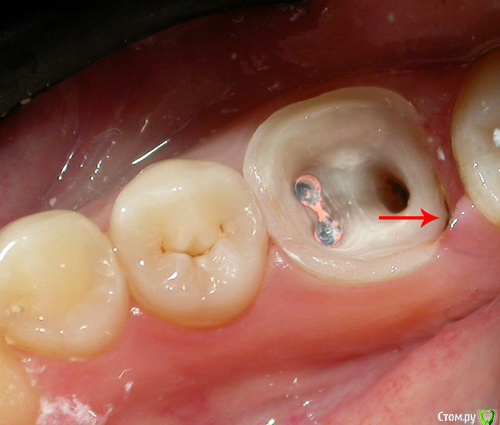

Denden Опубликовано 29 августа, 2016 Поделиться Опубликовано 29 августа, 2016 Добрый вечер, уважаемые специалисты! Сегодня ставил вкладку под коронку. Зуб был очень плохой, над деснами уже почти ничего не оставалось, по краям эмаль, внутри мягкая темная ткань. Перед тем, как стоматолог начала устанавливать вкладку (т. е. после очистки зуба от мягких тканей и вообще от всего лишнего) попросил зеркало, чтобы посмотреть подготовленное место. Увидел много остаточных темных пятен, разрозненных, преимущественно по труднодоступным углам, темно-коричневых. Не могу сказать, твердые они были или нет. Спросил у стоматолога, она сказала, что это сам зуб такой под эмалью, что это убирать не обязательно. Сейчас это уже все под коронкой, не могу показать, но тревога осталась, качественно ли подготовлено все под коронку. Скажите, обязательно ли под вкладкой должно быть все светлое, безо всяких темных островков? Сейчас смог сделать снимок того, что есть (пока нет самой коронки). И по краям видны темные участки, показал стрелками. Это не совсем то, но похоже. То, что уже зацементировано, было более темного цвета. PS: Есть также сомнение, что цена за все по московским меркам приемлемая. Каналы уже были до этого запломбированы, поэтому работа конкретного этого стоматолога заключалась в очистке зуба от всего лишнего до начала корней, вкладка, коронка. За все 14 тыс., хотя до этого другой врач в той же стоматологии говорила, что обойдется все примерно в 8 тыс. Спасибо! Ссылка на комментарий

Denden Опубликовано 29 августа, 2016 Автор Поделиться Опубликовано 29 августа, 2016 Нашел похожее по цвету и характеру пятно. Только у меня их было больше. Этот снимок не мой! Ссылка на комментарий

anvladd Опубликовано 29 августа, 2016 Поделиться Опубликовано 29 августа, 2016 (изменено) Переживать не стоит, похоже что оставили пигментированные ткани, а на вашем фото зуб еще не обточен под коронку,то что показано стрелками сточится. Не понятно только почему не заточили сразу,после фиксации вкладки. Изменено 29 августа, 2016 пользователем anvladd 1 Ссылка на комментарий